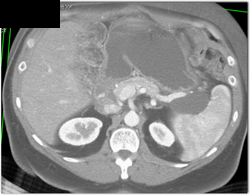

Diagnosis

Intraductal Papillary Mucinous Neoplasm (IPMN)